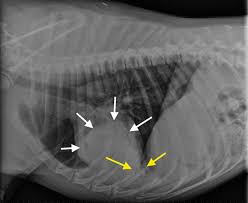

Your dog's chest may enlarge due to the tumor present. If the dog coughs once or twice, it's of no concern, but if. It is estimated that 25% of dogs with a lung tumor show no related signs of cancer. The dog is not coughing up mucus) although the cough may produce small amounts of phlegm or blood. They are rare in both species, but slightly more common in dogs.

Signs of lung cancer in dogs many dogs with a lung tumor show no related symptoms, while other dogs may display one or more of the following symptoms depending on the size and location of the tumor: Carcinomas are malignant tumors that develop from the epithelial tissues in the lungs. The clinical sign characterized as abnormal more common in dogs with lung cancer is a. Your dog's chest may enlarge due to the tumor present. Cancer of the lungs is a progressive disease, meaning it gets worse over time.

Your dog's chest may enlarge due to the tumor present. They are rare in both species, but slightly more common in dogs. Lung cancer in dogs symptoms the symptoms of lung cancer are coughing (which may produce phlegm or blood), exercise intolerance (lethargy), loss of weight or loss of appetite and other respiratory symptoms such as difficulty breathing or shortness of breath. All breeds and both genders appear to be equally affected. The dog may cough up blood, but not mucus. At this stage, the tumor can be removed through surgery. Cancer of the lungs is a progressive disease, meaning it gets worse over time. Most primary lung tumors are diagnosed at an average age of 10 to 12 years in dogs. Symptoms symptoms of lung cancer are coughing (which may also produce phlegm or blood), exercise intolerance (lethargy), weight loss or loss of appetite, and other respiratory signs such as trouble breathing or shortness of breath. #1 lack of appetite as with people, dogs suffer the negative effects of cancer treatments, including loss of appetite. Respiratory problems such as a cough that doesn't respond to treatment is an early indicator that dog lung cancer may be the underlying cause of the condition. Your veterinarian may recommend an fna and cytology or a biopsy, to confirm the diagnosis, and determine exactly what kind of lung cancer is present. Coughing doesn't automatically signal cancer;